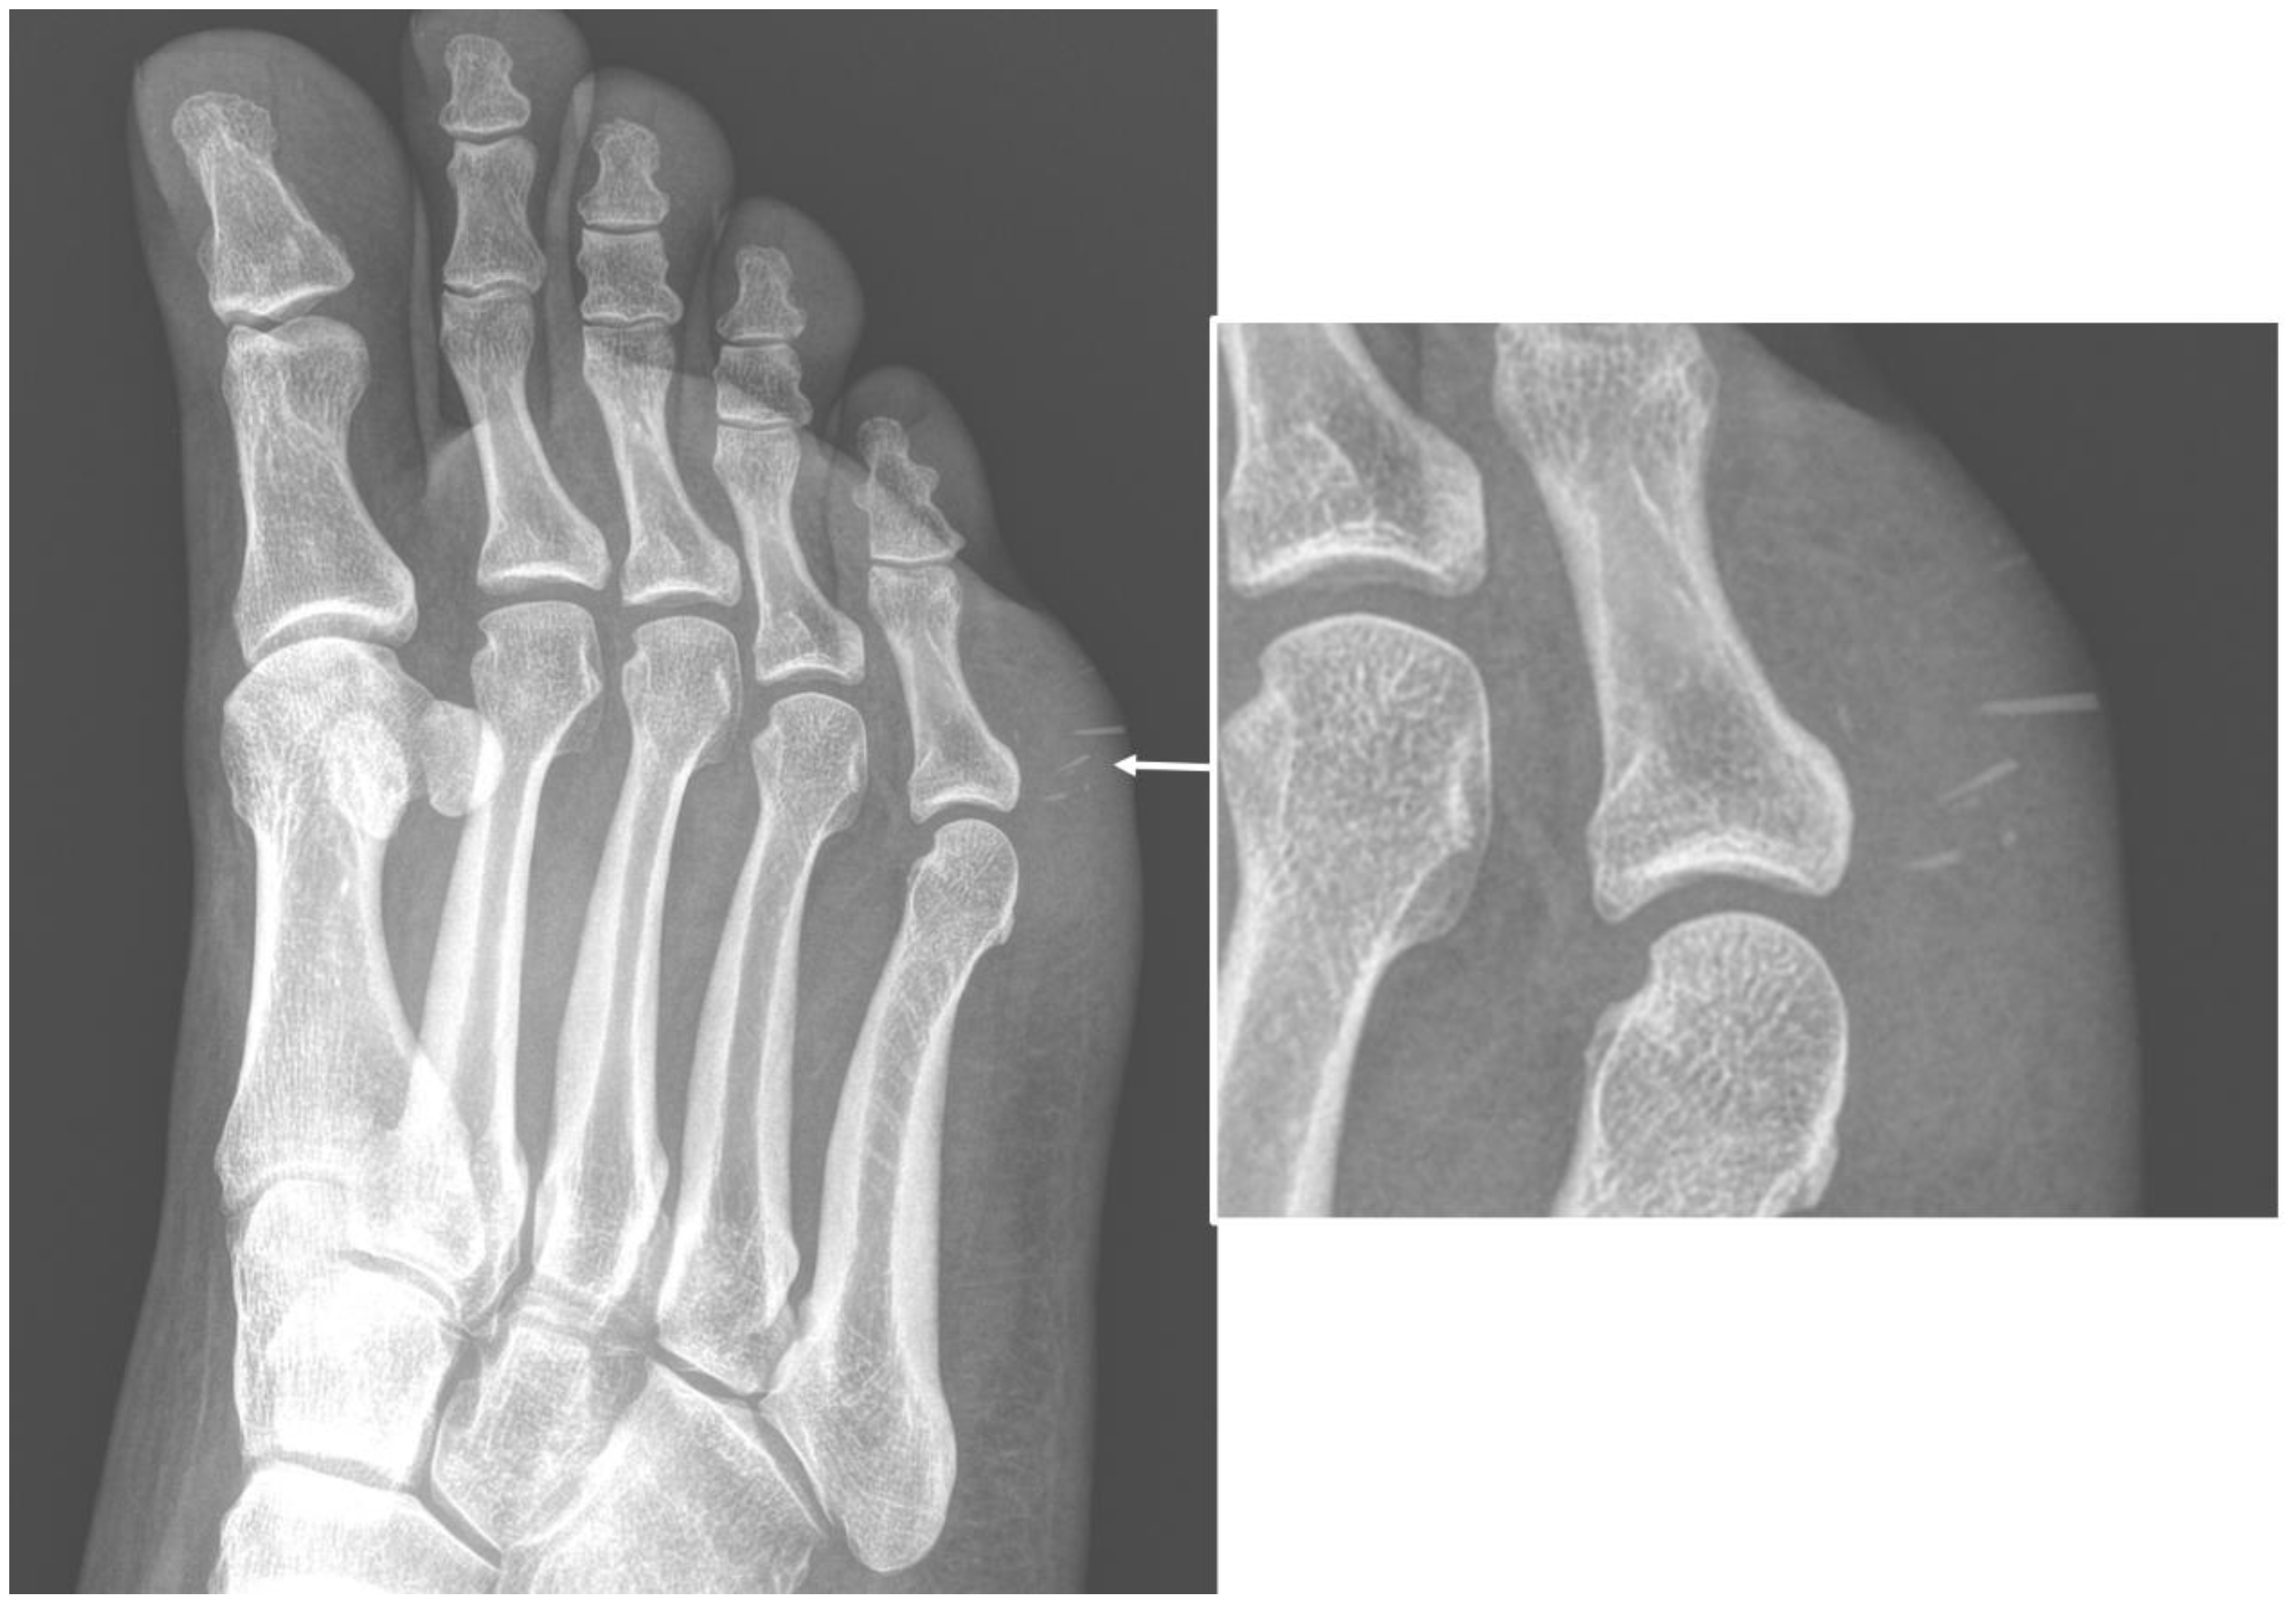

2.3. Soft-Tissue Foreign Body

- Carneiro, B.C.; Cruz, I.A.N.; Chemin, R.N.; Rizzetto, T.A.; Guimarães, J.B.; Silva, F.D.; Junior, C.Y.; Pastore, D.; Ormond Filho, A.G.; Nico, M.A.C. Multimodality imaging of foreign bodies: New insights into old challenges. Radiographics 2020, 40, 1965–1986. [Google Scholar] [CrossRef] [PubMed]

- Jarraya, M.; Hayashi, D.; de Villiers, R.V.; Roemer, F.W.; Murakami, A.M.; Cossi, A.; Guermazi, A. Multimodality imaging of foreign bodies of the musculoskeletal system. AJR Am. J. Roentgenol. 2014, 203, W92–W102. [Google Scholar] [CrossRef] [PubMed]

- Johnson, P.W.; Collins, M.S.; Wenger, D.E. Diagnostic utility of t1-weighted mri characteristics in evaluation of osteomyelitis of the foot. AJR Am. J. Roentgenol. 2009, 192, 96–100. [Google Scholar] [CrossRef]